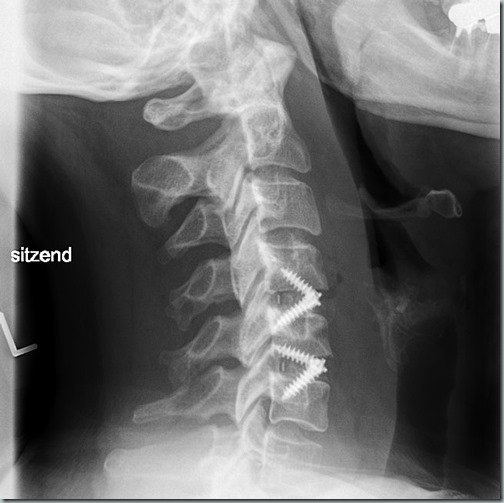

… bin ich. Im Krankenhaus herrschte absolute Bettennot und alles, was irgendwie nach Hause konnte, wurde heute nach Hause entlassen. Also auch ich. Im Gepäck Arztbrief, Krankmeldung bis nächsten Freitag (die dürfen nur eine Woche nach Krankenhaus) und Termin für den Kontrolltermin am 18.1.24. Bis dahin: immer ruhig mit den jungen Pferden. Auf meinen Röntgenbildern habe ich dann auch erst zu Hause gesehen, das die Cages doch mit Schrauben fixiert worden sind. Gibt mir persönlich ein wenig mehr Sicherheit Smiley.